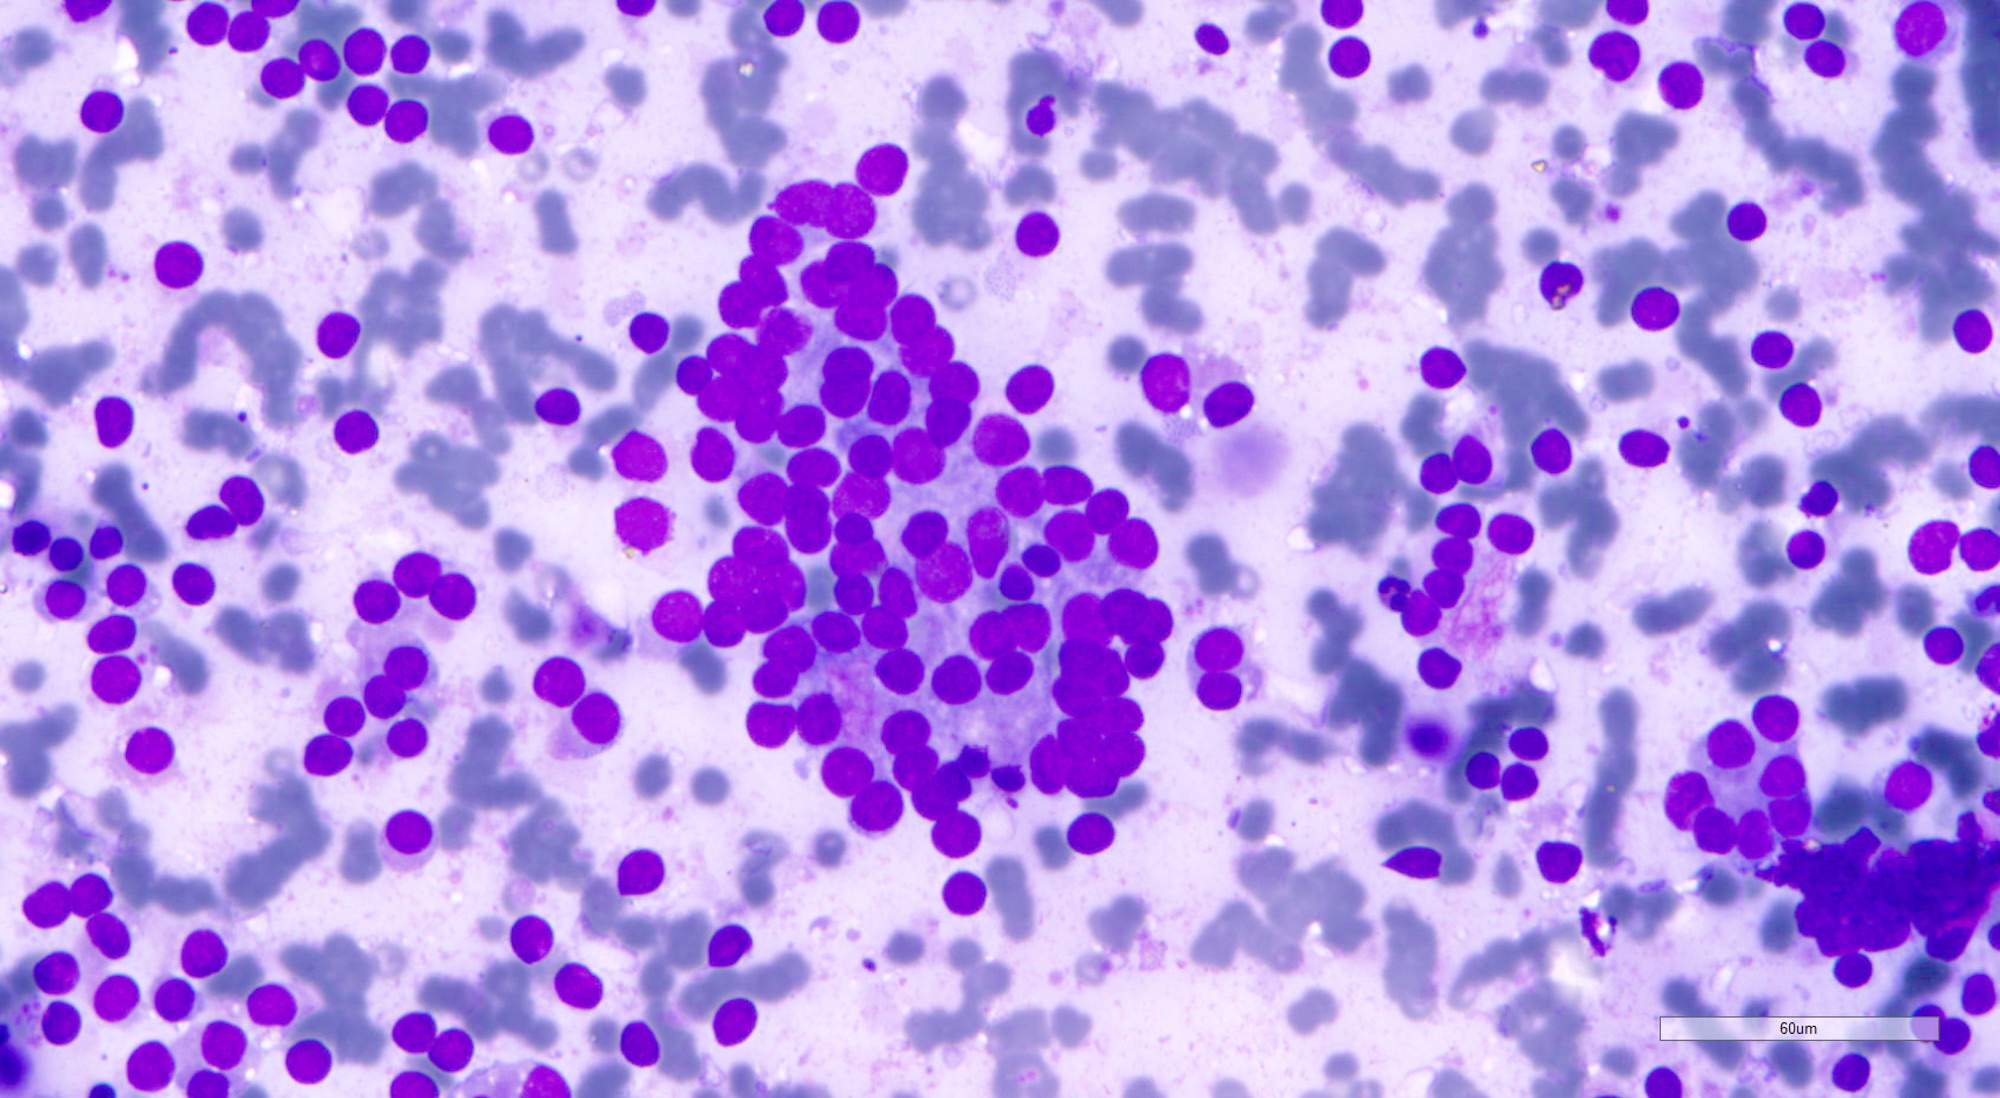

Cytology description

- Cellular aspirate (Korean J Pathol 2013;47:61, J Pathol Transl Med 2018;52:110)

- Cellular crowding

- Variable number of singly dispersed cells

- Microfollicular and solid / trabecular variants: numerous microfollicles, may have scant luminal colloid; absent or minimal background colloid

- Normofollicular and macrofollicular variants: monolayer sheets of follicular cells, abundant colloid; may mimic benign follicular nodule

- Hyperfunctioning follicular adenoma and follicular adenoma with papillary hyperplasia: monolayer sheets of polygonal cells with abundant cytoplasm, flame cells and occasionally, papillary fragments

- Uniform small round to ovoid nuclei, smooth nuclear margin, fine nuclear chromatin

- Absent nuclear features of papillary thyroid carcinoma

- The Bethesda System for Reporting Thyroid Cytopathology (TBSRTC) IV (follicular neoplasm / suspicious for a follicular neoplasm [FN / SFN]), III (atypia of undetermined significance [AUS A]) or II (benign) (Thyroid 2017;27:1341, Clin Endocrinol (Oxf) 2018;88:936)

- Cannot rule out follicular thyroid carcinoma based on cytologic findings

Cytology images